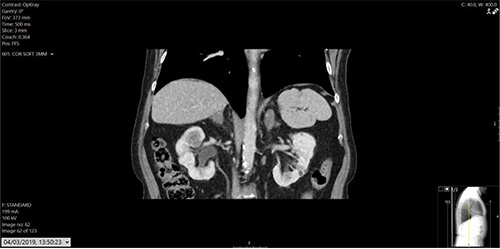

Figure 1: Initial CT of patient.

Blood work reported estimated glomerular filtration rate (eGFR) of 26, creatinine 161, and normal liver functions tests (LFTs). The CT at initial presentation with renal cancer and the recent contrast CT chest, abdomen and pelvis are shown in Figures 1-3. MRI of the skull reported a 3.3x2.3cm soft tissue heterogeneous lesion involving the parietal bone and invading the dura (Figure 4). Ultrasound-guided scalp biopsy showed infiltration of fibrous tissue by sheets of epithelioid tumour cells with abundant clear cytoplasm and intervening prominent blood vessels. The tumour cells expressed RCC, CD10 and PAX 8. They did not express CK7, CK20, TTF-1, Gata3 and WT-1. The conclusion was metastatic RCC.